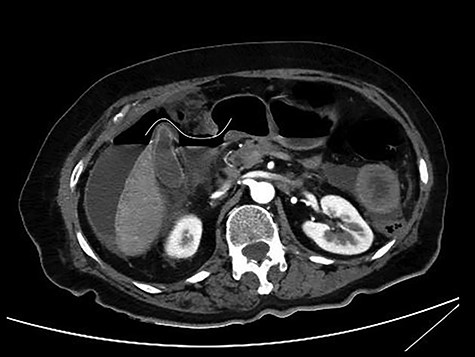

The patient was afebrile but hemodynamically unstable, with 115 bpm and a systolic pressure of 80 mmHg on presentation. Clinical examination revealed abdominal distension, diminished bowel sounds and severe tenderness with peritoneal signs in all of the abdominal quadrants. Her laboratory blood examination showed elevated number of neutrophils (7.77 K/μl), elevated C-reactive protein value (82.46 mg/dl) and decreased Na+ (119 mEq/l). After initial resuscitation, a computed tomography (CT) scan was performed. It showed free abdominal air and fluid in the peritoneal cavity, indicating an intestinal perforation (Figs 1–3).

CT multiplanar reconstruction (upper level, supine position) shows free air in continuity with intraluminal (duodenum) air. Notice the presence of free fluid in mesenteric pouches (stars), as well as encapsulated in the right paracolic gutter (arrows) and Douglas space (long arrow).